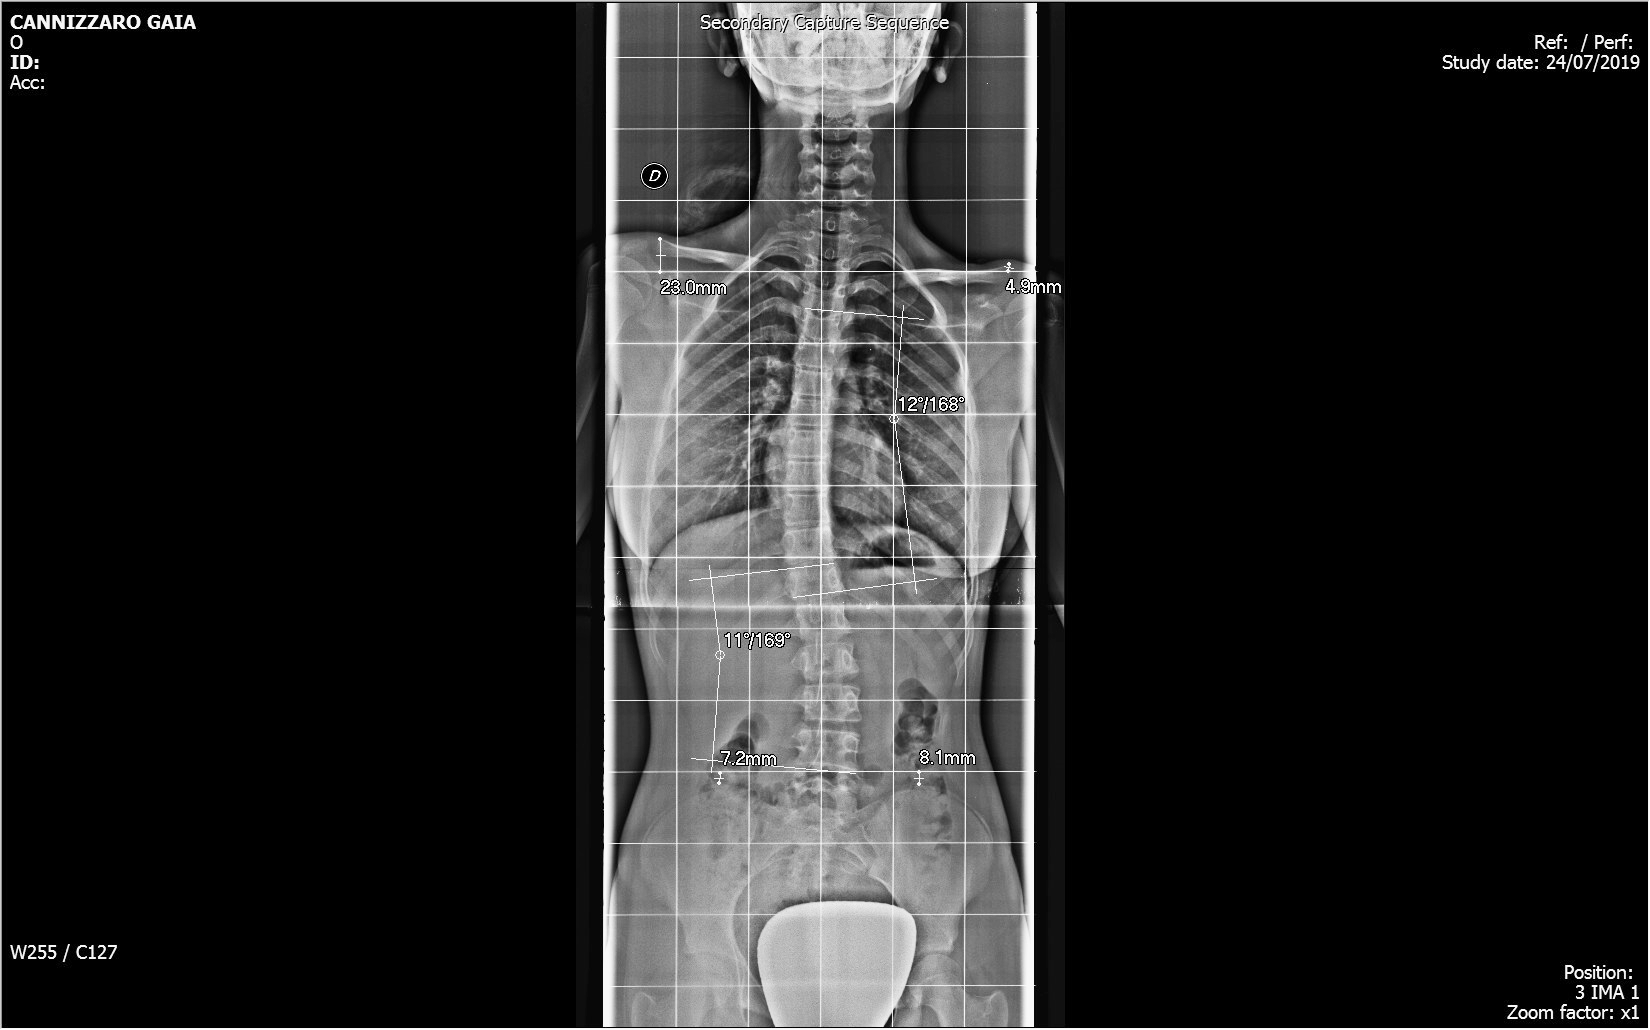

Nel Centro di Radiologia Muglia - Rago - Scaletta si eseguono tutti gli esami di routine dello scheletro, degli organi toraco-addominiali e gli esami contrastografici per lo studio della patologia intestinale ed in particolare la videofluorografia delle vie digestive superiori. La struttura si avvale di apparecchiature moderne e all’avanguardia, che ne fanno un innovativo centro di radiologia digitale a Bagheria e nei comuni limitrofi.

Il centro di radiologia è dotato di un sistema wireless per l'invio immediato delle immagini radiografiche ad un computer, mantenendo una qualità elevata ed evitando superflue esposizioni dei pazienti ai raggi X.

Tutte le immagini acquisite, trattate con un sofisticato post processing, vengono registrate su un supporto digitale (DVD).

Il personale medico è altamente specializzato anche per l’esecuzione degli esami pediatrici con l’uso, ai fini diagnostici, della dose minima di radiazioni ionizzanti.